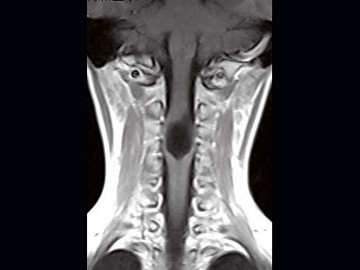

女,9岁,颈部疼痛、活动受限2个月,MRI检查如图,最可能的诊断为()

A.室管膜瘤

B.星形细胞瘤

C.神经鞘瘤

D.髓内囊肿

E.脊膜瘤